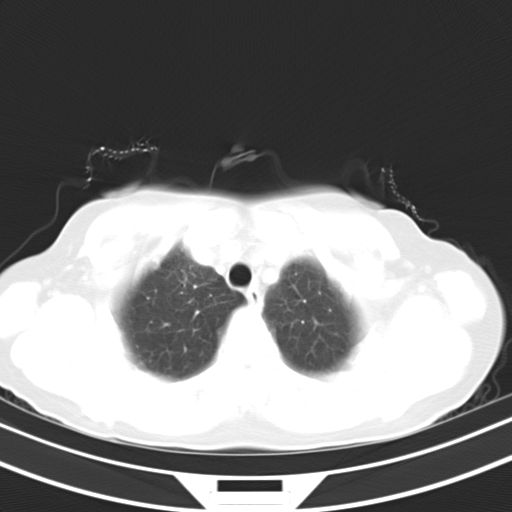

女,47岁,咳嗽胸痛一个星期,我们考虑肺结核,左下肺病灶肿瘤像不像,请高手指点。急。

炎性灶;【1楔状实变影,有支气管气象,2近端纹理影增重】

右肺为炎性改变,左肺病灶影像所见1、楔状实变影,边缘呈刀切样,见支气管气象,2、近端纹理影增重。

两肺病变考虑炎症可能性大。(左肺病变呈楔状实变影,有支气管气象,近端纹理影增重)。

考虑右肺上叶前段及左肺舌叶炎症,建议抗炎治疗后复查除外结核。

左肺舌叶病灶呈扇形分布,其内可见支气管影,胸膜面光滑,不支持肿瘤病变。